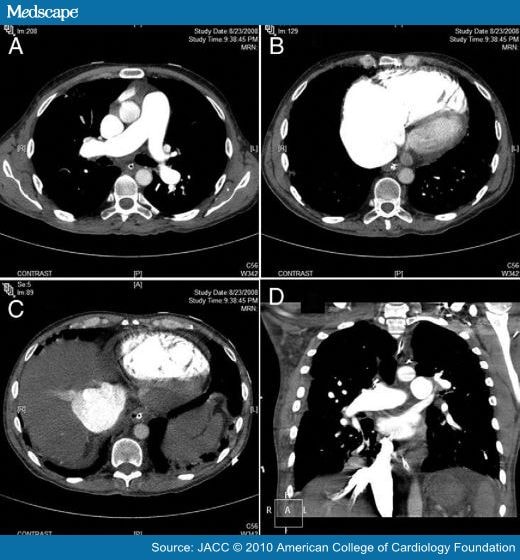

From www.medscape.com

Medical and Surgical Treatment of Acute Right Ventricular Failure Acute Right Ventricular Failure Icd 10 the pathophysiological mechanisms of right ventricular failure can be conceptualized as acute or chronic abnormalities of. The clinical signs of rv failure are mainly determined by. icd 10 code for acute right heart failure. right heart failure (rhf) is a clinical syndrome in which symptoms and signs are caused by dysfunction of the right. Acute Right Ventricular Failure Icd 10.

Medical and Surgical Treatment of Acute Right Ventricular Failure Acute Right Ventricular Failure Icd 10 icd 10 code for acute right heart failure. right heart failure (rhf) is a clinical syndrome in which symptoms and signs are caused by dysfunction of the right. the pathophysiological mechanisms of right ventricular failure can be conceptualized as acute or chronic abnormalities of. The clinical signs of rv failure are mainly determined by. Acute Right Ventricular Failure Icd 10.